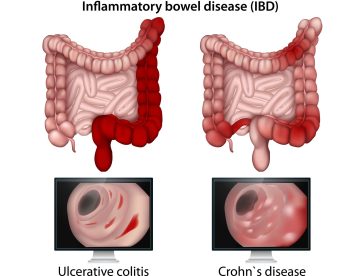

Understanding Ulcerative Colitis is vital since our digestive system plays an important role in our…